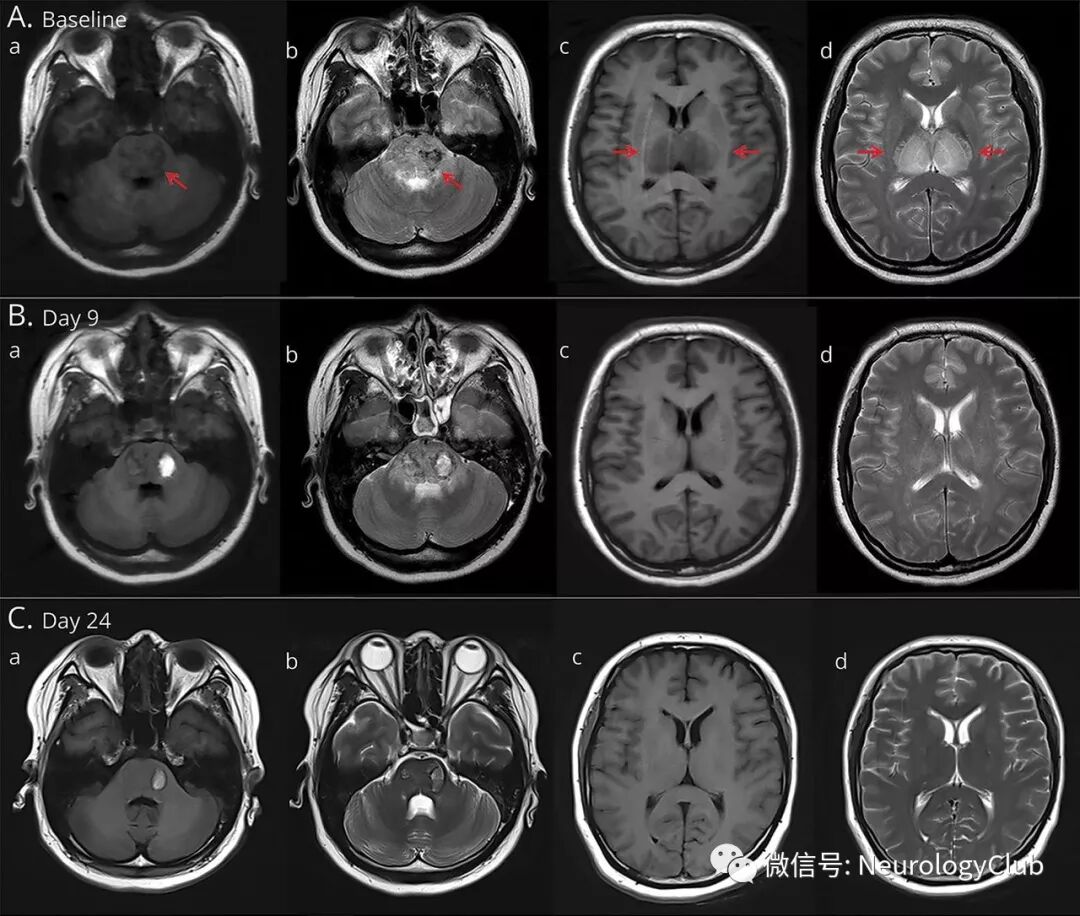

(图2:A:入院时,ADC和DWI可见双侧丘脑靶样病灶和水肿;B:第9天,ADC和DWI可见病灶较前消退)